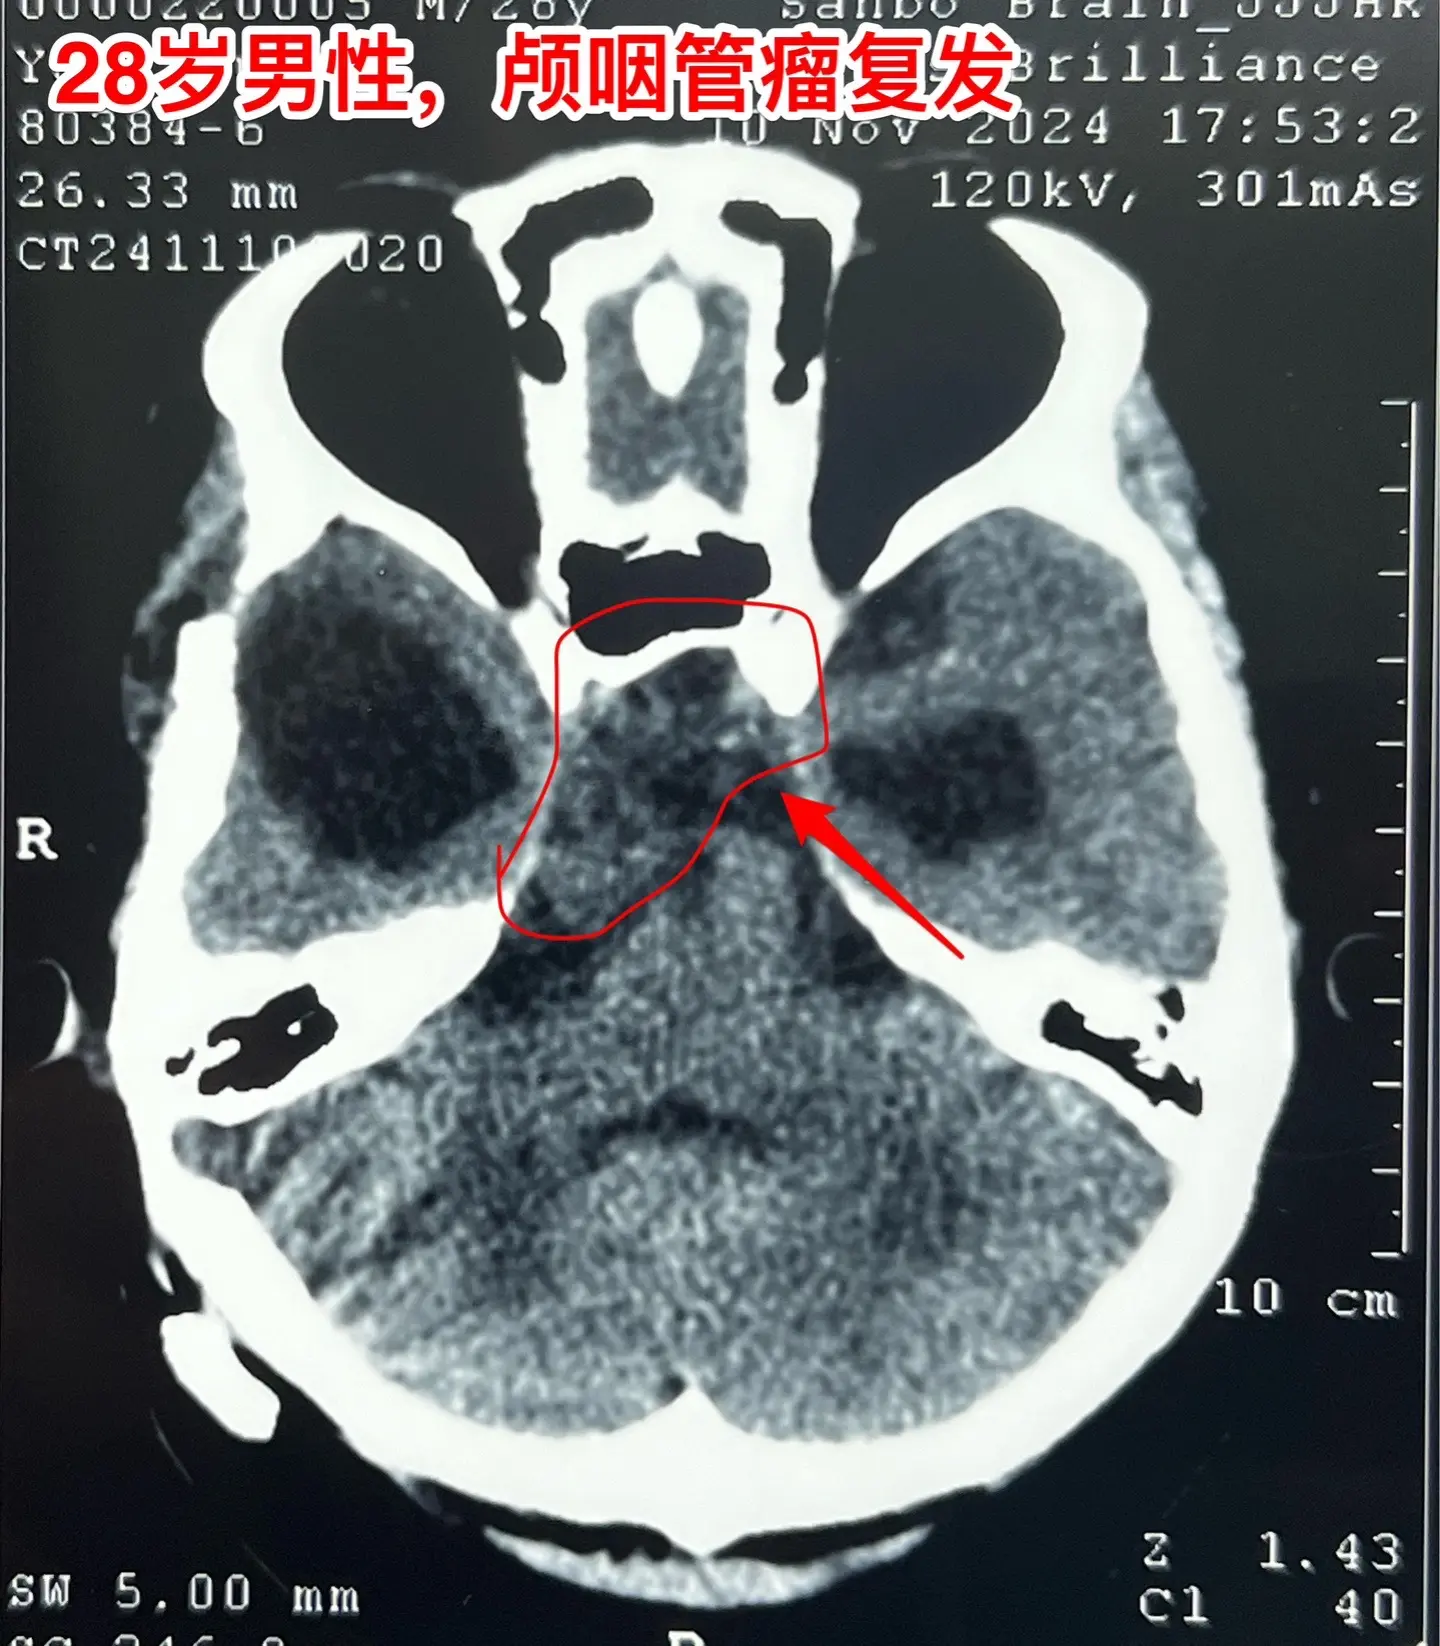

颅咽管瘤四次复发,为挽救视力只能作手术。28岁的四川小伙子,因颅咽管瘤在四川省先后作了四次开颅手术、一次脑室腹腔分流术。2024.6因肿瘤复发还作了一次伽马刀治疗,2024.9复查磁共振显示肿瘤体积在增大。 患者左眼已经失明了,右眼视力也在下降。为了挽救视力,他还是找我想再作一次手术,而且他的心态还是积极乐观的。 11月19日作了手术。原以为这个颅咽管瘤是不可能得到完全切除的,然而手术过程中却发现肿瘤不是一个整体,而是由四块肿瘤组成的,通过各个击破的方式将肿瘤完全切除了。病人右眼的视力也保住了。 希望肿瘤不再复发了!